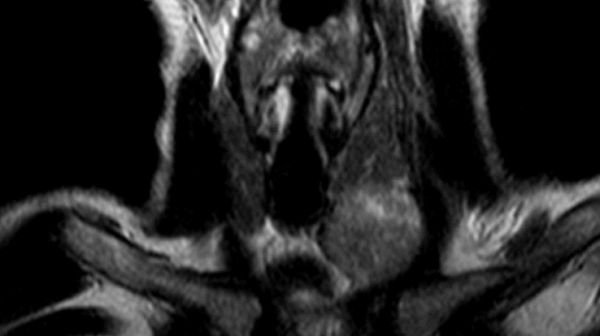

Опухоль щитовидной железы на МРТ

Новообразование (указано стрелкой) на МРТ щитовидной железы